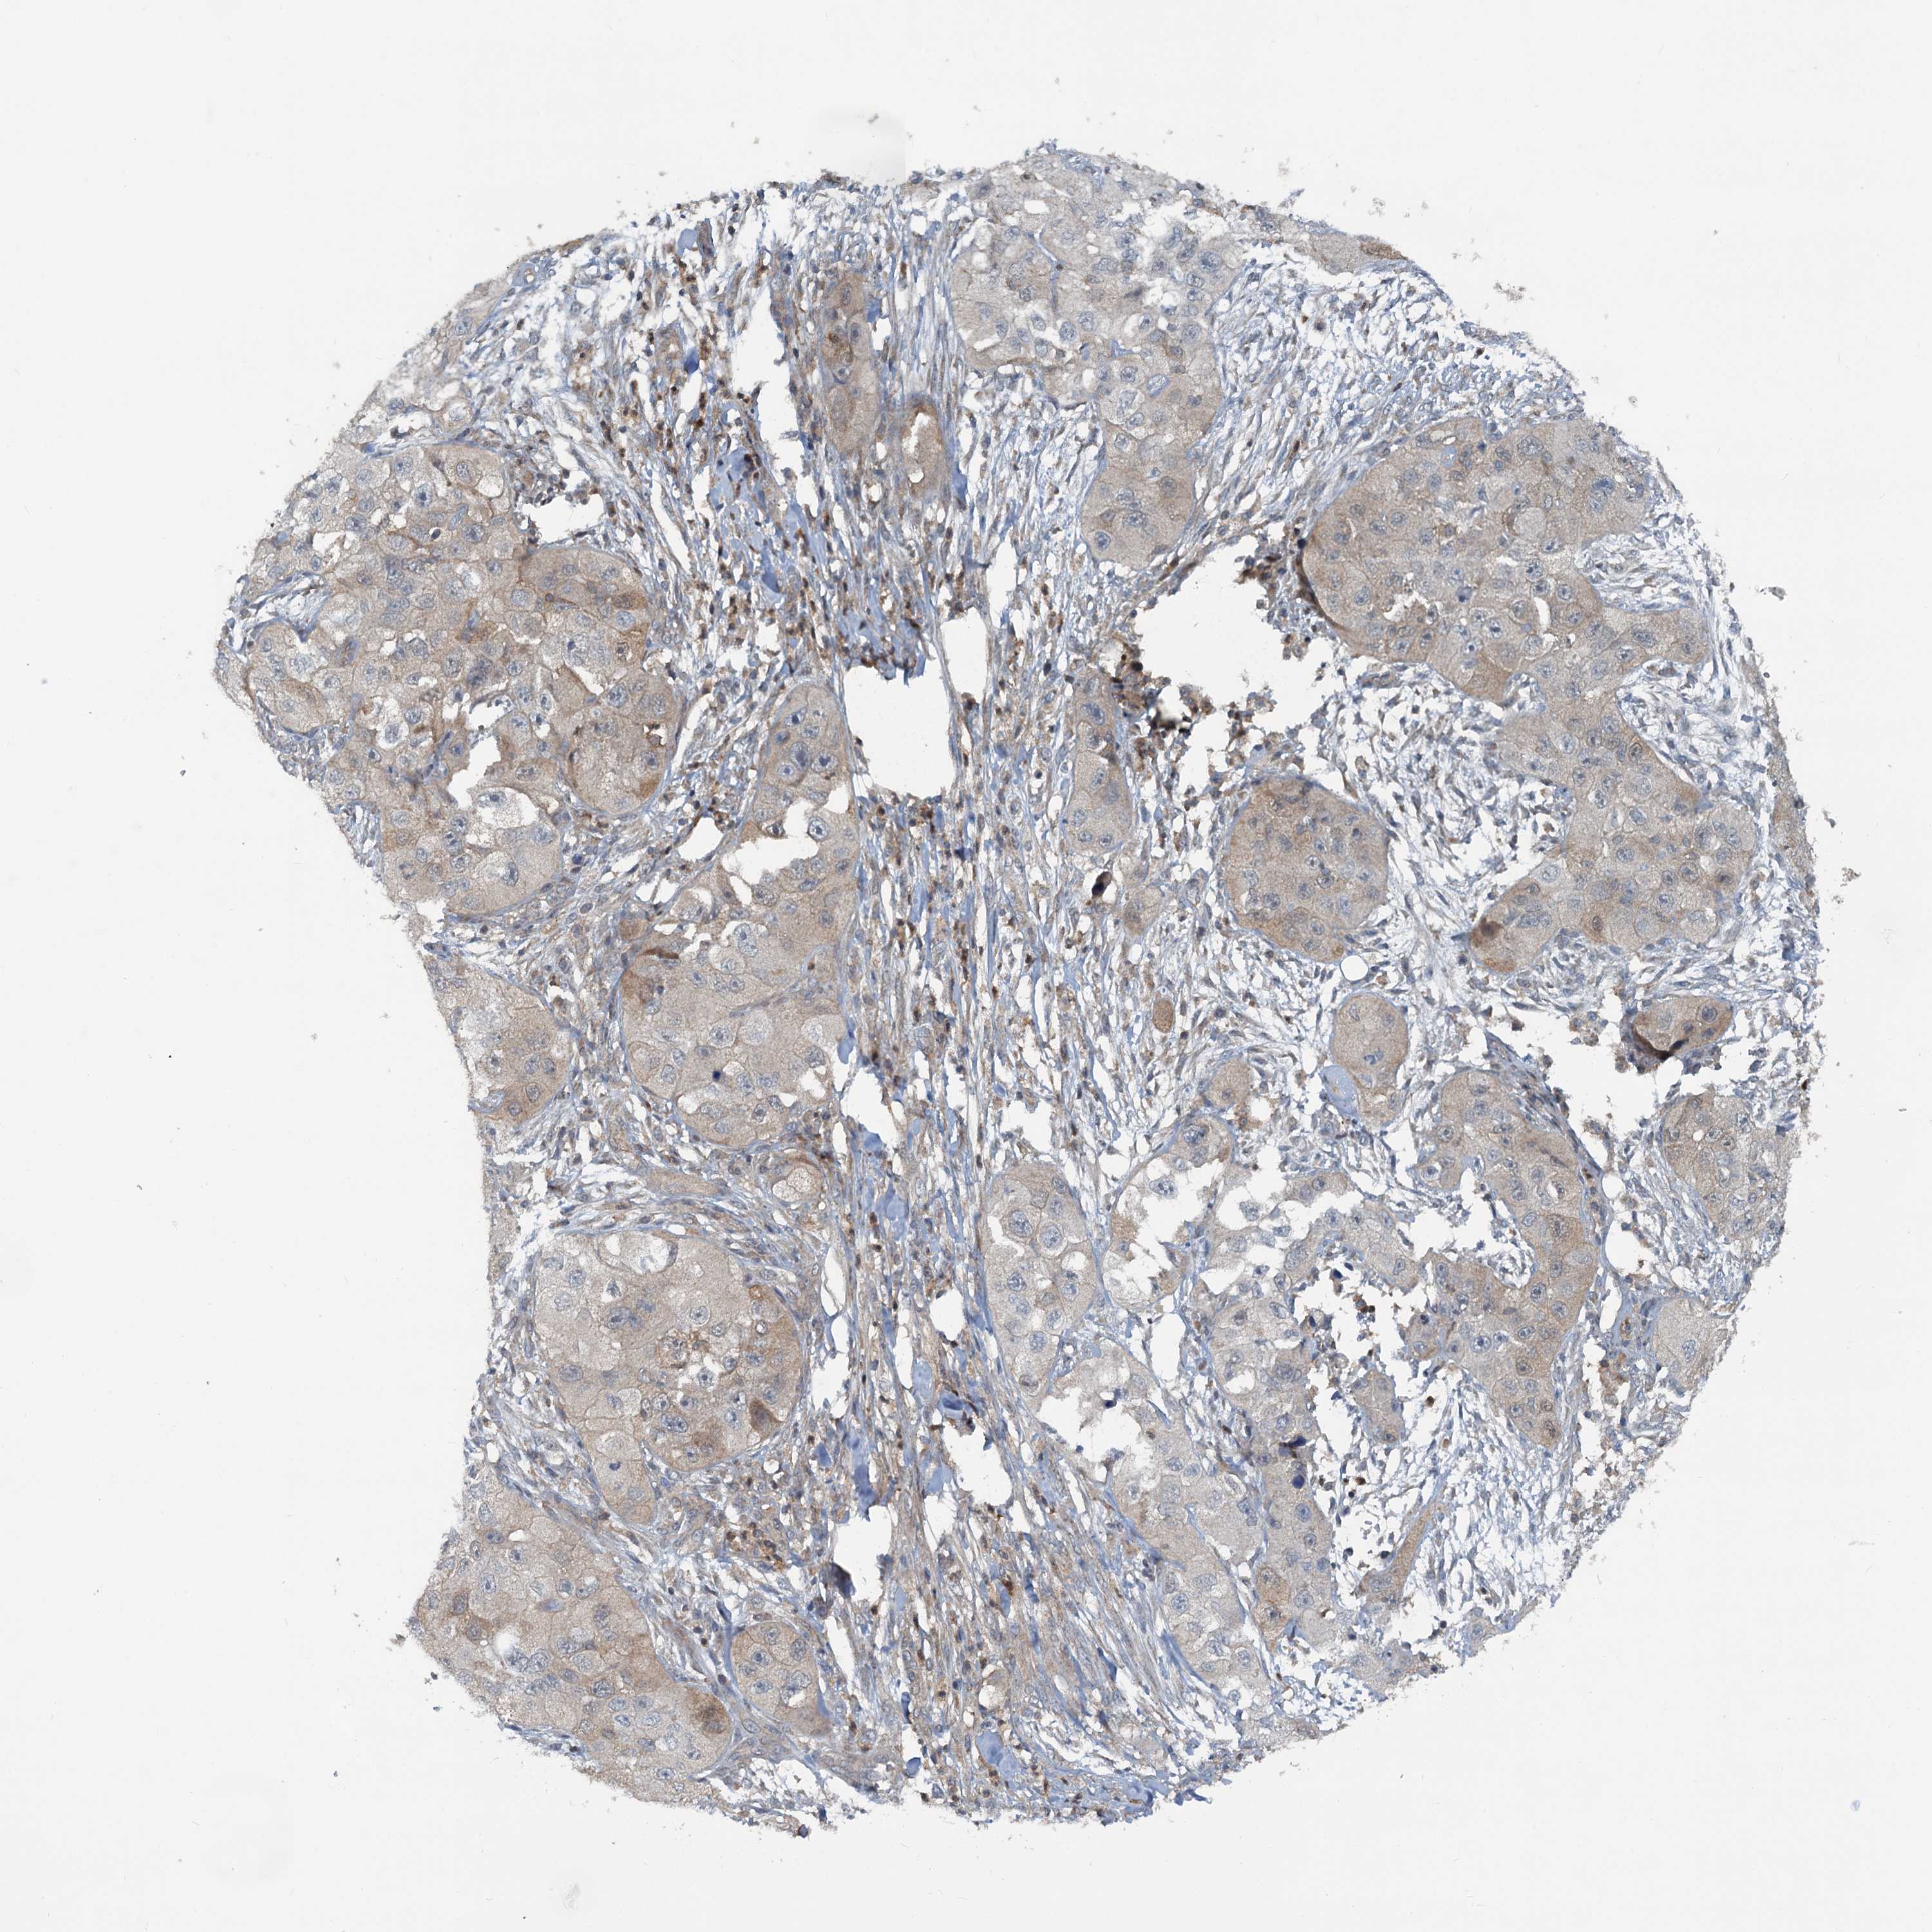

SKIN CANCER - Protein expressioni

A mouse-over function shows sample information and annotation data. Click on an image to view it in a full screen mode. Samples can be filtered based on level of antibody staining by selecting one or several of the following categories: high, medium, low and not detected. The assay and annotation is described here.

Antibody stainingi

Antibody staining in the annotated cell types in the current human tissue is reported as not detected, low, medium, or high, based on conventional immunohistochemistry profiling in selected tissues. This score is based on the combination of the staining intensity and fraction of stained cells.

Each image is clickable and will lead to virtual microscopy that enables deeper exploration of all samples and also displays staining intensity scores, fraction scores and subcellular localization as well as patient and tissue information for each sample.

Basal cell carcinoma